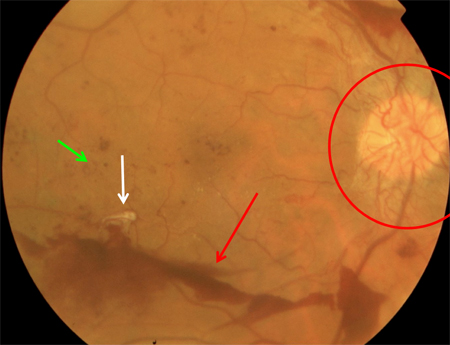

Non-proliferative diabetic retinopathy: intraretinal microvascular abnormality (IRMA; green arrow), venous beading and segmentation (blue arrow), cluster haemorrhage (red circle), featureless retina suggestive of capillary non-perfusion (white ellipse)

Courtesy of Moorfields Photographic Archive; used with permission